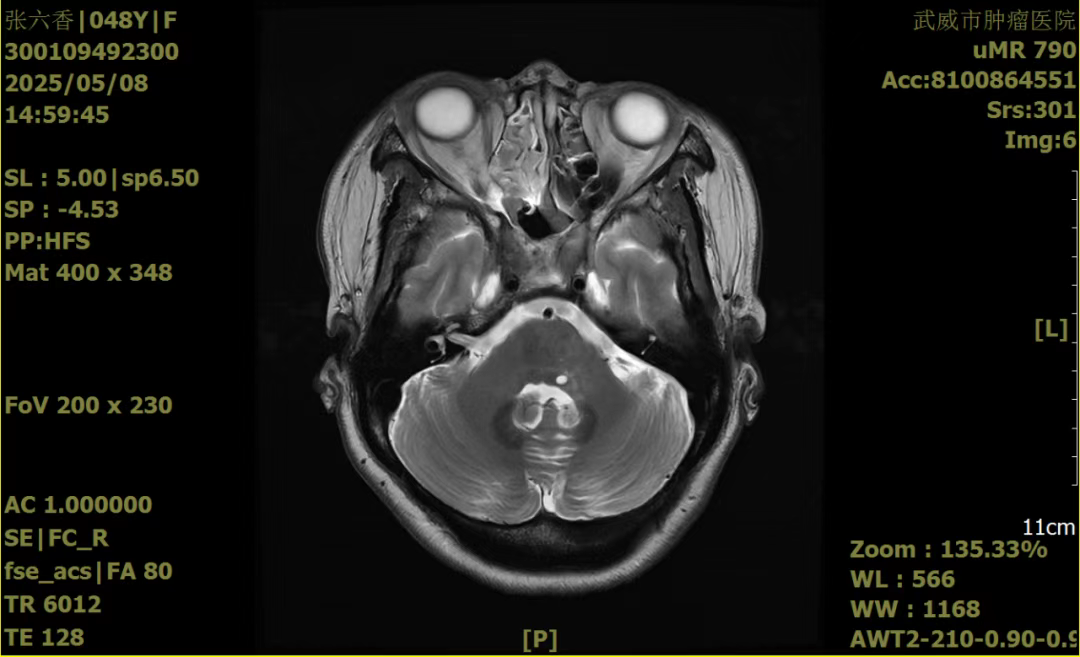

这个故事要从五年前说起,一场突如其来的疾病打破了张女士原本平静而幸福的生活,张女士被诊断为“脑胶质瘤”,并在南昌大学第二附属医院全麻下行了“经鼻窦垂体瘤切除术”。不料,却在术后一年又出现了恶心呕吐、头痛头晕,“复发”使张女士陷入无尽的痛苦、绝望,就在她和家人倍感无助、无望时,偶然看到关于重离子的一则报道,这不由得让张女士及家属燃起了一丝希望,他们立即与重离子中心马有国副院长取得联系,在马院长耐心细致的讲解后,跨越两千多公里,从老家飞到武威,来到了甘肃省武威肿瘤医院重离子中心放疗一科。经重离子专家团队会诊后,给予了碳离子治疗,DT:48GyE/16f,同步给予脱水、保肝、保护胃黏膜,营养等对症支持治疗,同时注重患者的心理疏导,帮助其树立抗癌信心,经过系统的治疗,患者病情好转,病灶较前明显缩小,生活质量显著提升。于2025年05月08日患者再次来院复查,病情平稳,精神状态良好。

治疗后